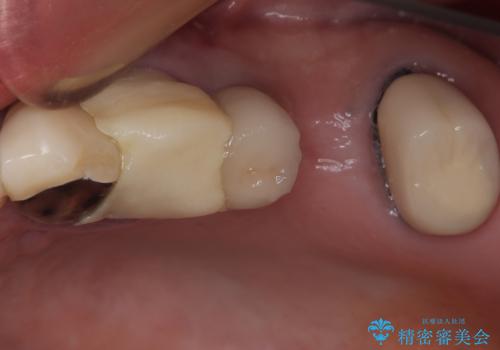

治療前、下顎前歯はほとんど見えない咬み合わせでしたが、矯正治療によりディープバイトが改善されました。

矯正治療中に前歯2本のクラウンは外れてしまい、途中仮歯に替える必要があったので期間は掛かりましたが、歯列も整い、負担のかからない咬み合わせを達成することができました。